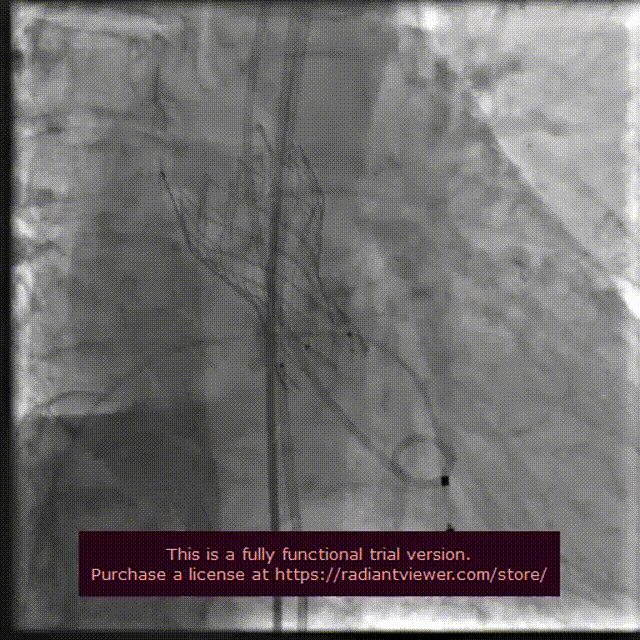

瓣膜完整形态

术者团队观察到瓣膜形态未能完全伸展,为取得更好治疗效果,后续予以后扩处理。采用18 mm球囊进行后扩后扩,行主动脉造影提示瓣膜置入位置良好、形态完整。